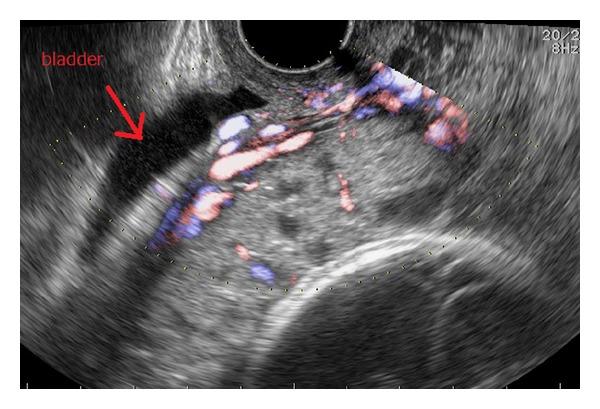

We report our experience with a case of presumptive cesarean scar pregnancy, based on detection of a gestational sac (GS) in early pregnancy at the site of a previous cesarean scar. The GS grew into the uterine cavity as the pregnancy progressed, showing an ultrasound image similar to that of a normal pregnancy. Thus, the pregnancy continued, resulting in a viable birth at 28 weeks of gestation. Cesarean scar pregnancy is classified as myometrial implantation or implantation growth into the uterine cavity. In the latter type, the gestational sac moves upward with increasing gestational weeks and it shows the same ultrasound image as a normal pregnancy. Therefore, the diagnosis must be made in the early pregnancy.